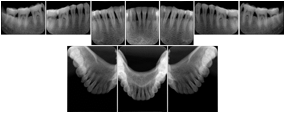

2. A patient requests cosmetic surgery to enhance their facial appearance. The case requires consultation between an orthodontist in New York and an oral surgeon in California. The cephalometric series of 2D projections constructed from the volumetric CT data that is used for the discussion is arranged by a Structured Display for transfer between the two practitioners.

Cephalometric Series Structured Display

Figure OO-2. Cephalometric Series Structured Display